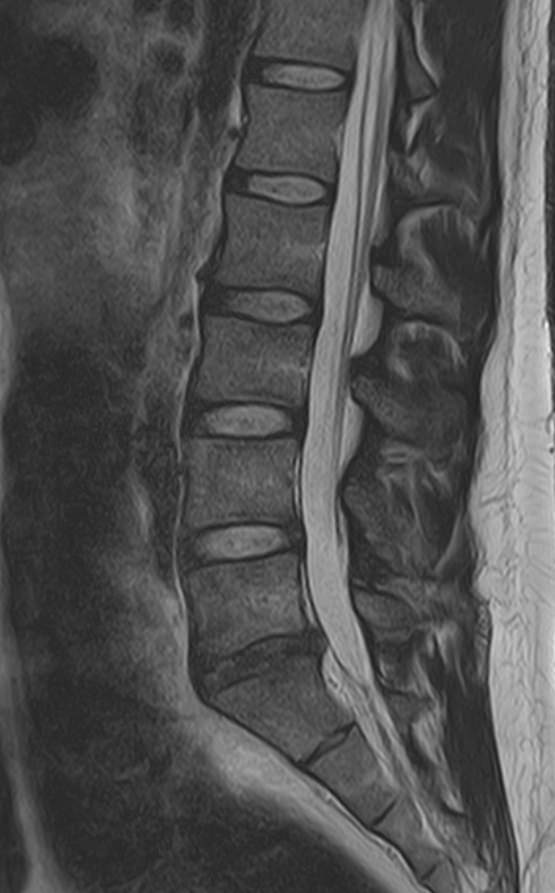

Пояснично-крестцовый отдел позвоночника выполняет основную опорную функцию, поддерживая устойчивость тела. Нижние отделы позвоночника и крупные суставы нижних конечностей, в частности, коленные суставы, испытывают интенсивные нагрузки, поэтому часто подвержены развитию воспалительных и дегенеративно-дистрофических заболеваний.

При сочетанном поражении этих анатомических областей целесообразно проведение комплексной МРТ, включающей обследование пояснично-крестцового отдела позвоночника и коленных суставов.

Томограф позволяет детально визуализировать состояние всех анатомических структур позвоночного столба на исследуемом уровне, костные структуры колена и окружающие мягкие ткани данных анатомических областей, включая мышцы, связки, нервные сплетение, сосуды.

• дегенеративно-дистрофические заболевания позвоночника: спондилез, спондилоартроз, остеохондроз;

• стеноз (сужение) позвоночного канала;

• грыжи межпозвонковых дисков (протрузии, экструзии);

• переломы позвонков, их смещение;

• спондилиты, гнойные артриты, сакроилеит, абсцессы околопозвоночных тканей и другие воспалительные заболевания, туберкулез;

• опухоли позвоночника и окружающих тканей;

• патологические изгибы позвоночника, сколиоз, усиленный или выпрямленный лордоз как нарушение статической функции позвоночника;

• аномалии строении позвоночника;